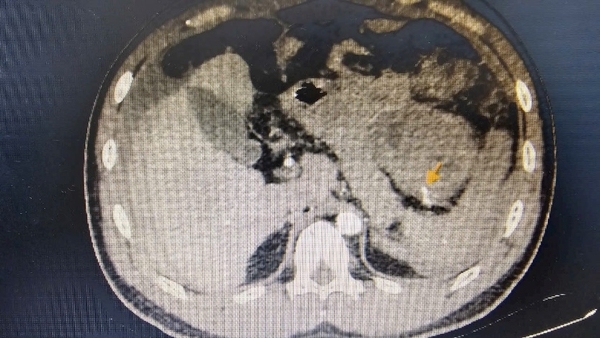

Sau khi hồi sức tích cực, bệnh nhân được chụp cắt lớp vi tính đa dãy (MSCT) ổ bụng và hình ảnh cho thấy: rất nhiều dịch máu trong ổ bụng, nguyên nhân do vỡ giả phình động mạch lách ngay vị trí rốn lách – thủ phạm gây xuất huyết ồ ạt.

Kết quả sau can thiệp: ổ giả phình được bít tắc hoàn toàn, nhu mô lách vẫn được nuôi dưỡng nhờ hệ bàng hệ. Sau 24 giờ, tình trạng bệnh nhân ổn định, không còn dấu hiệu mất máu, dẫn lưu ổ bụng ra khoảng 2 lít máu cũ.